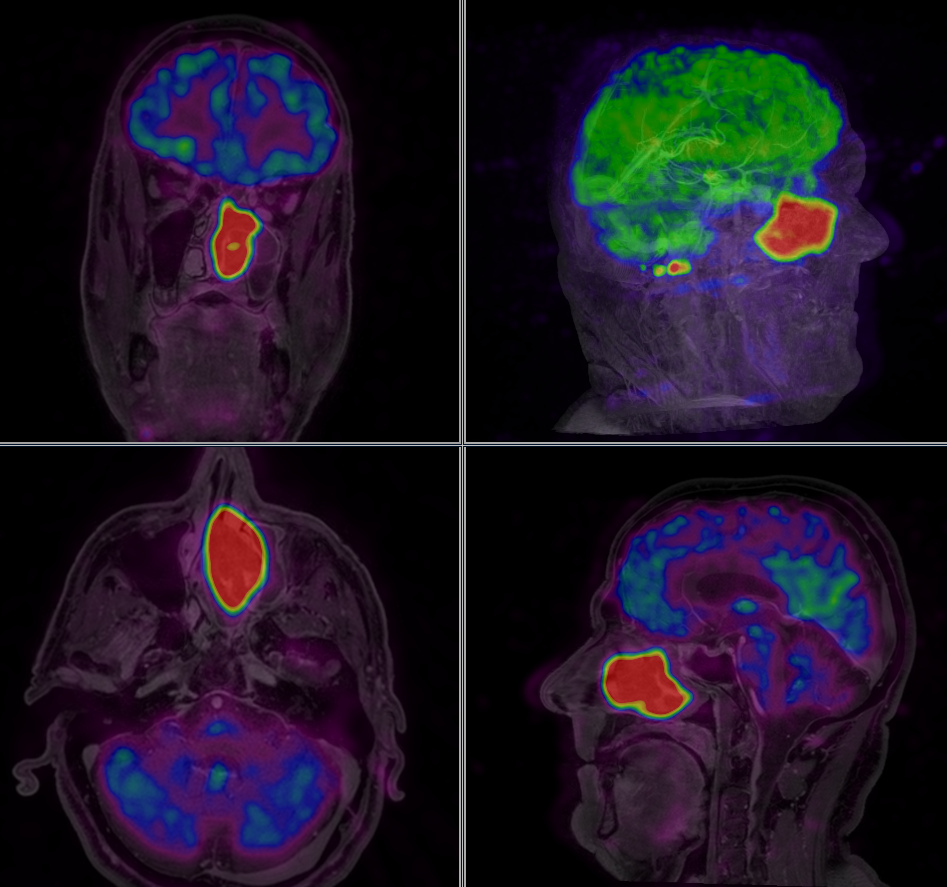

In another presentation, Anne Ducassou, M.D., from the Institut Claudius Regaud, IUCT-Oncopole, Toulouse, France, discussed findings from a study of all 177 children treated for ependymoma in France between 2000 and 2013. The children ranged in age from 1-23, with a median age of five. The researchers studied the characteristic of their disease as revealed by magnetic resonance imaging (MRI) scans, and specifically in those related to metabolism — for example perfusion (the blood flow created in the tumor), and the diffusion of intercellular water molecules, which also reflects the number of cells in the tumor. "We wanted to know whether these metabolic characteristics might have a role in the prognosis of local control of disease and in survival, and whether they might also be able to help us predict relapse, where the disease returns or reoccurs after a period of improvement," Ducassou said.

All radiation oncologists in France who had treated pediatric patients with ependymoma provided information to Ducassou's team. The researchers found that children with localized disease who had been treated with the high radiation dose of 59.4 Gy, in use since 2004, did better than those who had received the lower dose in use until that date. Of the 177 patients included in the study, the estimated overall survival and progression-free survival (where the disease remains but does not get worse) were 90 percent and 67 percent for patients who received a dose above 54 Gy, compared with 79 percent and 52 percent who received a lower dose.